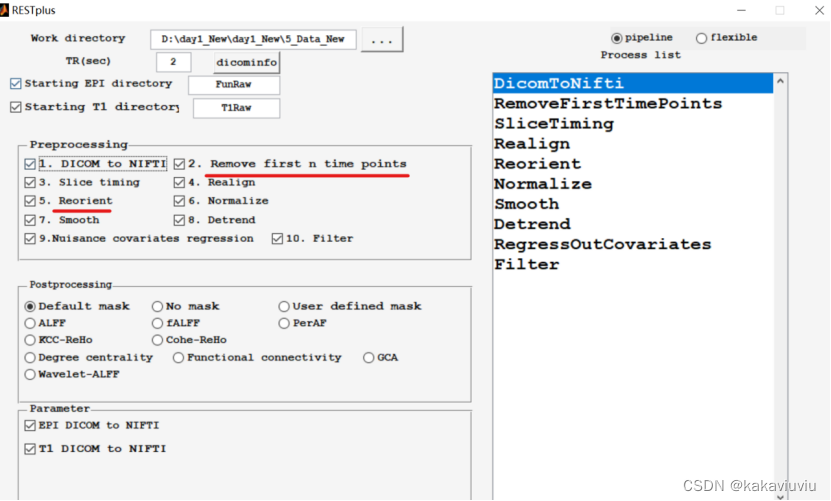

剩下几步用restplus做(实际上上述步骤都可以用restplus批量处理)

Restplus

Set path--add with subfolders-添加restplus的文件夹

打开pipeline

Matlab切路径到restplus

work directory选择所用文件的上一级文件夹

EPI directory选择功能像,T1 directory选择T1的文件夹(原始数据)

其中,2和5可选可不选

每一项的参数根据自己实际需要来调整即可(略)